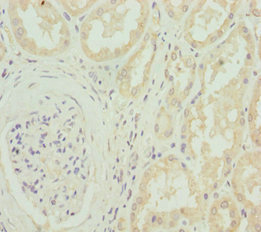

Immunohistochemistry of paraffin-embedded human kidney tissue using CSB-PA004411DSR1HU at dilution of 1:100